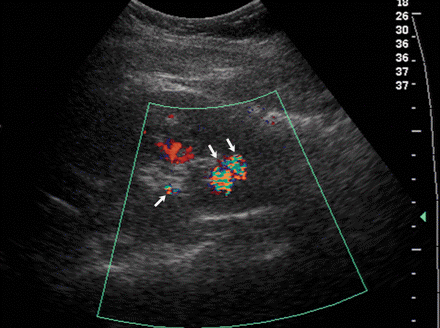

Twinkle artifact owing to renal calculi. (a) Longitudinal gray-scale US image shows a faintly echogenic region in the lower pole sinus but no definite renal stones. (b) Color Doppler US image depicts three calculi with twinkle artifact (arrows).